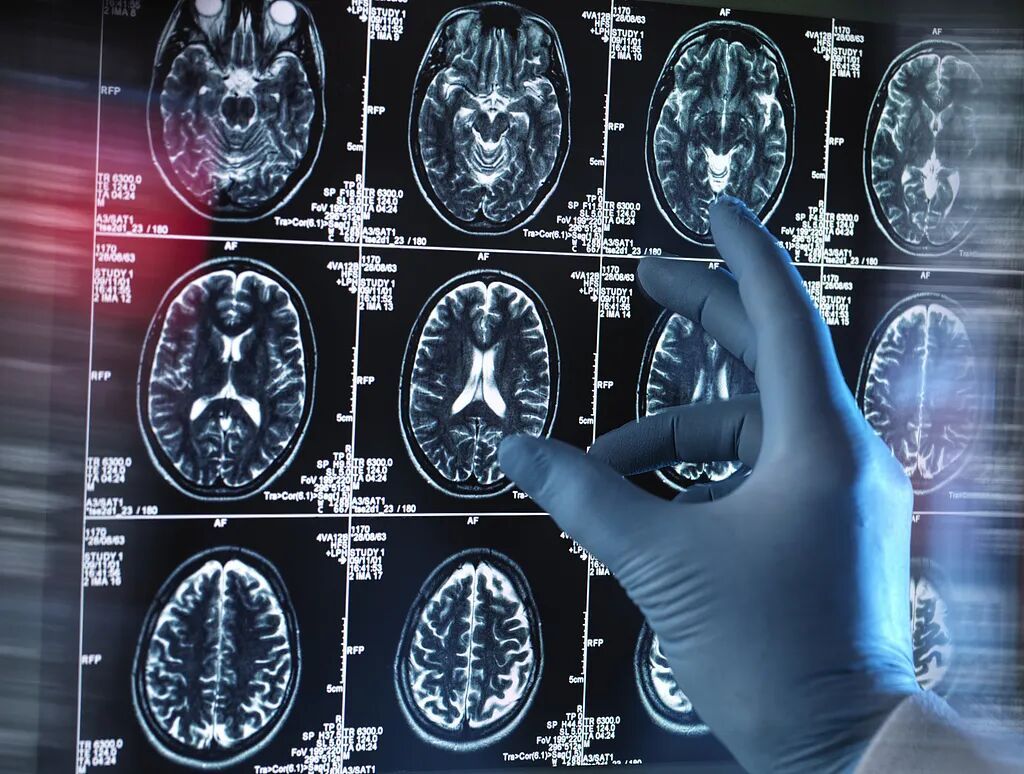

小王的头颅MR显示

右侧额叶萎缩、基底节区异常信号

医生首先考虑脑梗死

网络配图

进一步

颅内动脉CTA(CT血管造影术)

检查发现

↓↓↓

右大脑中动脉M1段重度狭窄(88%)

右大脑中动脉M2段重度狭窄(71%)

右侧椎动脉V4段中度狭窄(48%)

左侧大脑中动脉M1段还有一个直径约3.8mm的动脉瘤

这三处狭窄和一粒动脉瘤,就像三颗随时可能引爆的“炸弹”,一旦堵塞或破裂,轻则偏瘫失语,重则危及生命。追问病史发现,小王同学发现高血压1年,但从未规律服药,也没有监测血压。